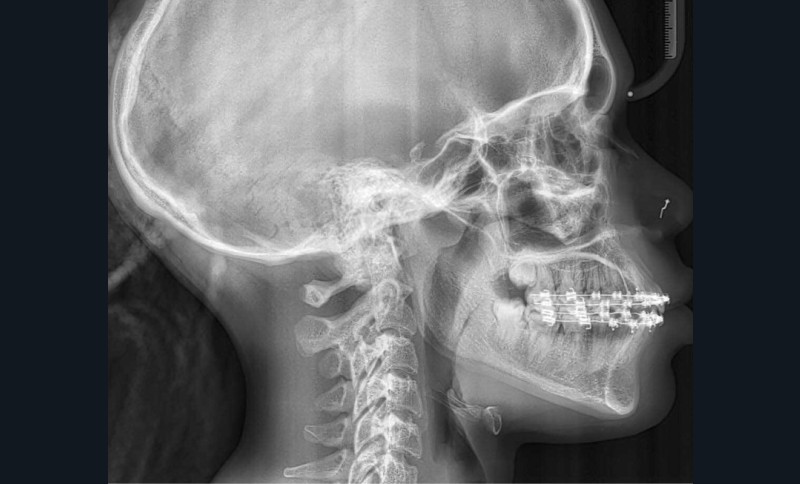

La téléradiographie de profil montre une Classe II squelettique par biprognathie, avec proalvéolie et vestibuloversion de l’incisive mandibulaire.

À l’examen extra-oral, la patiente présente un profil biprognathe associé à une Classe II squelettique modérée dans un contexte de normodivergence. L’angle naso-labial apparaît ouvert, le sillon labio-mentonnier est marqué et une prochéilie mandibulaire est observée. Le sourire se révèle disharmonieux, avec une faible visibilité des dents maxillaires.